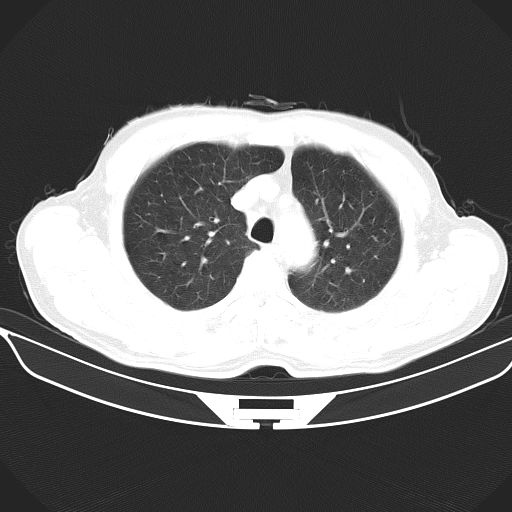

以下是引用心路寻觅在2010-3-1 10:23:00的发言:[br]1、考虑左肺上叶周围型肺癌[br]2、右上肺陈旧性病灶。[br][br][本贴已被 心路寻觅 于 2010-3-1 10:40:18 修改过]

以下是引用shuiyuan在2010-3-1 10:45:00的发言:[br]考虑左肺上叶中心型肺癌伴阻塞型炎症,邻近胸膜受侵。